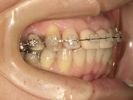

30代女性

事故のため、前歯を2本失いました。

インプラントと矯正治療をしました。

| 治療前 | ||

| インプラント後、仮歯を入れました。 | ||

| 矯正設置を着用し、歯列矯正を行いました。 | ||

| 治療後 | ||